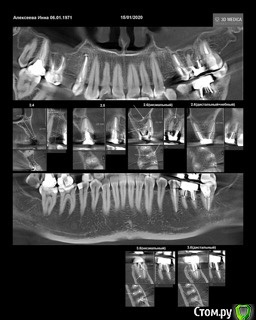

Уважаемые доктора. В 7-ой нижний зуб слева была установлена керамическая вкладка. Началось жжение языка, дискомфорт. Долго думали, решили высверлить вкладку. Ортопед изготовил новую керамическую вкладку, потом решили перелечить каналы, так как нашли дополнительный канал. Затем ортопед установил заготовленную ранее вкладку и зуб начал болеть. Жжение возобновилось и добавилось к боли. Доктор установил временную коронку, корректировал ее несколько раз, так как десна воспалена и в итоге сказал ,если беспокоит надо удалять. Пожалуйста выскажите своё мнение по моей ситуации. Добавляю снимки после перелечивания каналов, после установки вкладки, КТ до лечения. Благодарю за ответы.

post-11530-0-96750100-1600953974_thumb.jpeg